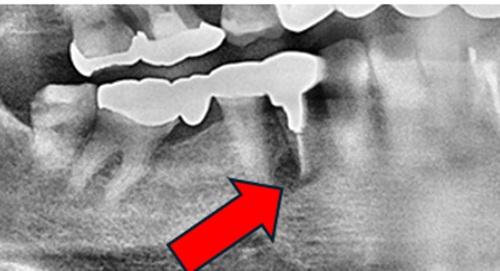

レントゲン検査では、右下の根の先が黒くなり、膿が溜まっているのが分かります。膿がたまっているので、歯ぐきが紫色になり、腫れています。

しかし、今回の症例は、前医の先生が、根の治療を根の先まで防腐剤を入れて行っていたようだが、予後は悪く、腫れと痛みがでたのです。

網目状に神経が分岐しているために、菌の繁殖を止める事ができない状態と考えられます。あくまで、根の治療は、メインの根の根管しか、封鎖できません。